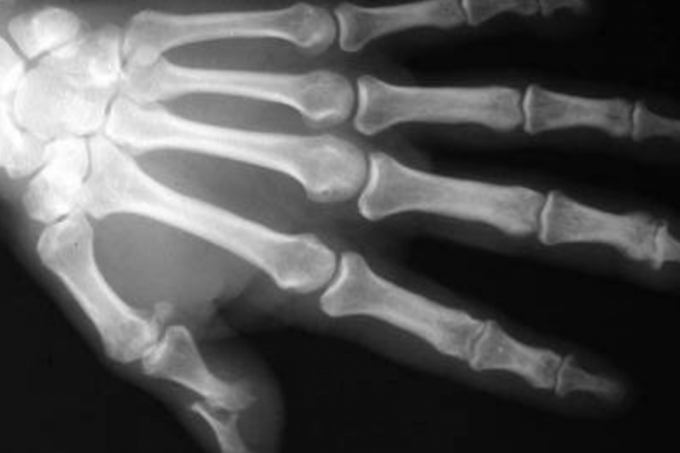

Um corpo mumificado do século XVI encontrado no Equador pode ajudar a traçar a história de uma dolorosa enfermidade que se estendeu da América para a Europa. "É uma múmia extremamente importante para a história das doenças", disse à AFP o legista francês Philippe Charlier. O especialista esteve nesta semana no laboratório do Instituto Nacional de Patrimônio Cultural (INPC) para analisar os restos de seu novo "paciente", que contém as pistas para reconstruir a origem da poliartrite reumatoide e a travessia para o velho continente.

Por ter ficado em um ambiente frio e seco, o corpo não foi atacado por larvas e moscas, o que permitiu a conservação dos tecidos com as características da poliartrite reumatoide.

Trata-se de uma doença inflamatória das articulações própria da América que chamou a atenção de Charlier, que estudou os restos mortais de Hitler, Descartes, Robespierre e do primeiro exemplar descoberto do homem de Cromañón.

"É uma enfermidade muito comum hoje em dia, mas sua origem é americana, antes da chegada de Cristóvão Colón", explicou Charlier, acrescentando que a múmia de Guano "pode ser o elo perdido (...) que nos permitiria entender como esta doença que era originalmente americana, se tornou global por hibridação, pelo choque entre dois mundos".